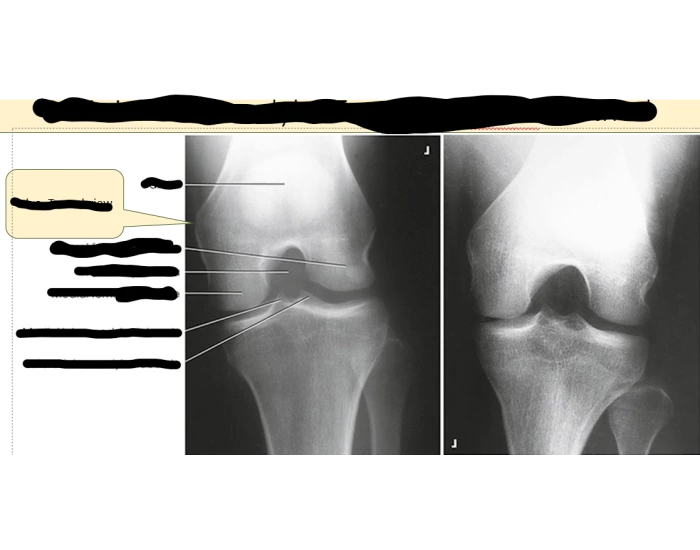

The intercondylar fossa of femur (intercondyloid fossa of femur, intercondylar notch of femur) is a deep notch between the rear surfaces of the medial and lateral epicondyle of the femur, two protrusions on the distal end of the femur (thigh bone) that joins the knee. On the front of the femur, the condyles are but much less prominent and are separated from one another by a smooth shallow articular depression called the patellar surface because it articulates with the posterior surface of the patella (kneecap).

On a lateral radiograph, it is evident as Blumensaat's line.